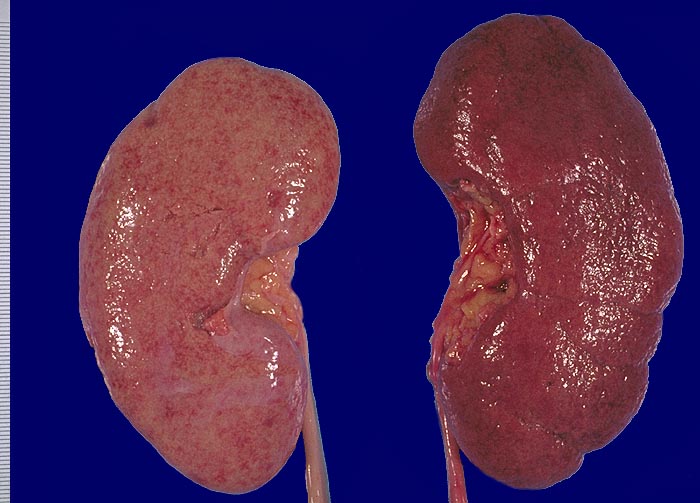

Im allgemeinen ist die Niere infolge von Glomerulumhypertrophie und Tubulushyperplasie vergrössert und derb, die Oberfläche ist granuliert. Bei schwerer Atherosklerose und fortgeschrittener Niereninsuffizienz kann die Niere auch normal gross oder verkleinert sein. Die Kombination von nodulärer Glomerulosklerose, hyalinen Schlingenkappen (=Proteinthromben in den Glomerulumschlingen (> 1916)) oder Kapseltropfen (> 1907) und Arteriolosklerose in Vas afferens und efferens ist beweisend für eine diabetische Nephropathie. Jede einzelne Läsion für sich genommen ist aber unspezifisch. Eine noduläre Glomerulosklerose kann auch vorkommen bei membranoproliferativer Glomerulonephritis (> 2652), Leichtkettenglomerulopathie oder Amyloidose (> 2019). Der nodulären Glomerulosklerose geht bei Diabetikern eine diffuse Glomerulosklerose (> 1906) voraus. Dabei zeigen die glomerulären Basalmembranen und das Mesangium eine progrediente gleichförmige Verbreiterung. Bei der nodulären und diffusen Glomerulosklerose handelt es sich aber wahrscheinlich um zwei pathogenetisch unterschiedliche, sich überlagernde Krankheitsbilder. Typisch bei Diabetikern ist im Unterschied zur arteriellen Hypertonie die Arteriolosklerose von Vas afferens und efferens (> 1911) und oft auch der Vasa recta. Intrarenale Arterien können eine Atherosklerose mit Atheromen zeigen. Subendotheliale Proteinablagerungen teilweise mit Verschluss der Glomerulumschlingen (Schlingenkappen) und knotige Proteinablagerungen in der Bowman'schen Kapselbasalmebran (Kapseltropfen) gehören zu den sogenannten exsudativen Läsionen (> 1919) (> 1920) der diabetischen Nephropathie und führen zu Synechien sowie zur globalen Glomerulosklerose. Gleichzeitig mit den Glomerulumveränderungen treten tubuläre Basalmembranverbreiterungen auf, später eine Tubulusatrophie und interstitielle Fibrose mit Begleitentzündung. Auch die Basalmembranen der peritubulären Kapillaren sind verdickt.

Makroskopie

Pathologischer Befund